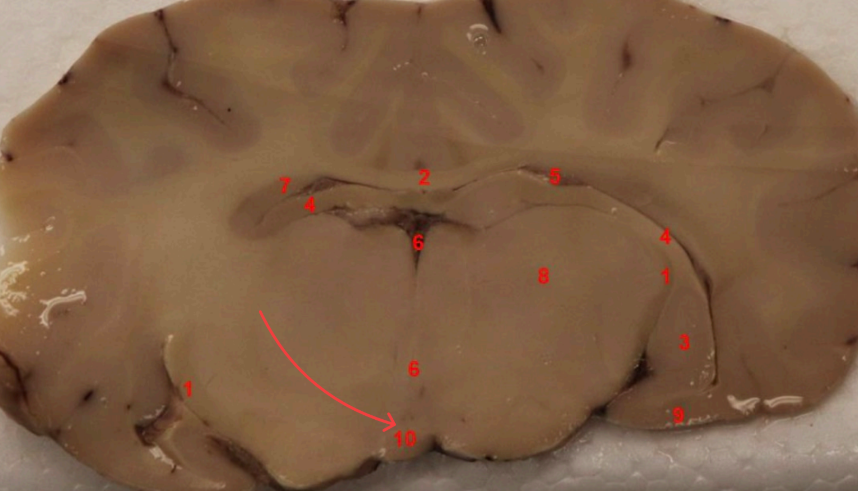

what nuclei is this ? function

Putamen, regulates motor control, including movement initiation, planning, and execution.

what area is this

external capsule

what is this

claustrum

what area is this?

extreme capsule

what nuclei is this?

Global Pallidus , regulates voluntary movement, suppresses unwanted motor activity, and influences reward/motivatio

what tract is this

Fornix

Global Pallidus

Putamen

Clustrum

what cortex is this

Insula, internal sensation (interoception_

what cortex is this?

piriform cortex

columns of fornix

septum

anterior comissure

priform cortex

optic tract

hypothalamus ( right beside 3rd ventricle)

what are these

cerebral penducles

what area is this , function?

Amygdala , processing emotion: fear, anxiety, and aggression